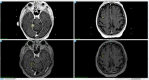

Case description: This report details the case of a 75-year-old male diagnosed with MCC following surgical excision of an inguinal mass, with subsequent adjuvant radiotherapy. Four months post-surgery, imaging revealed a pancreatic nodule and two cerebral lesions. The patient underwent Gamma Knife® stereotactic radiosurgery (GK-SRS) followed by adjuvant immunotherapy with avelumab. MRI follow-ups showed a significant reduction of the cerebellar lesion and full remission of the frontal lesion, with stable remission noted at one year. The patient remained asymptomatic and continued immunotherapy without neurological deficits.